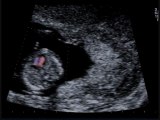

Plica nucale aumentata

2009-05-26